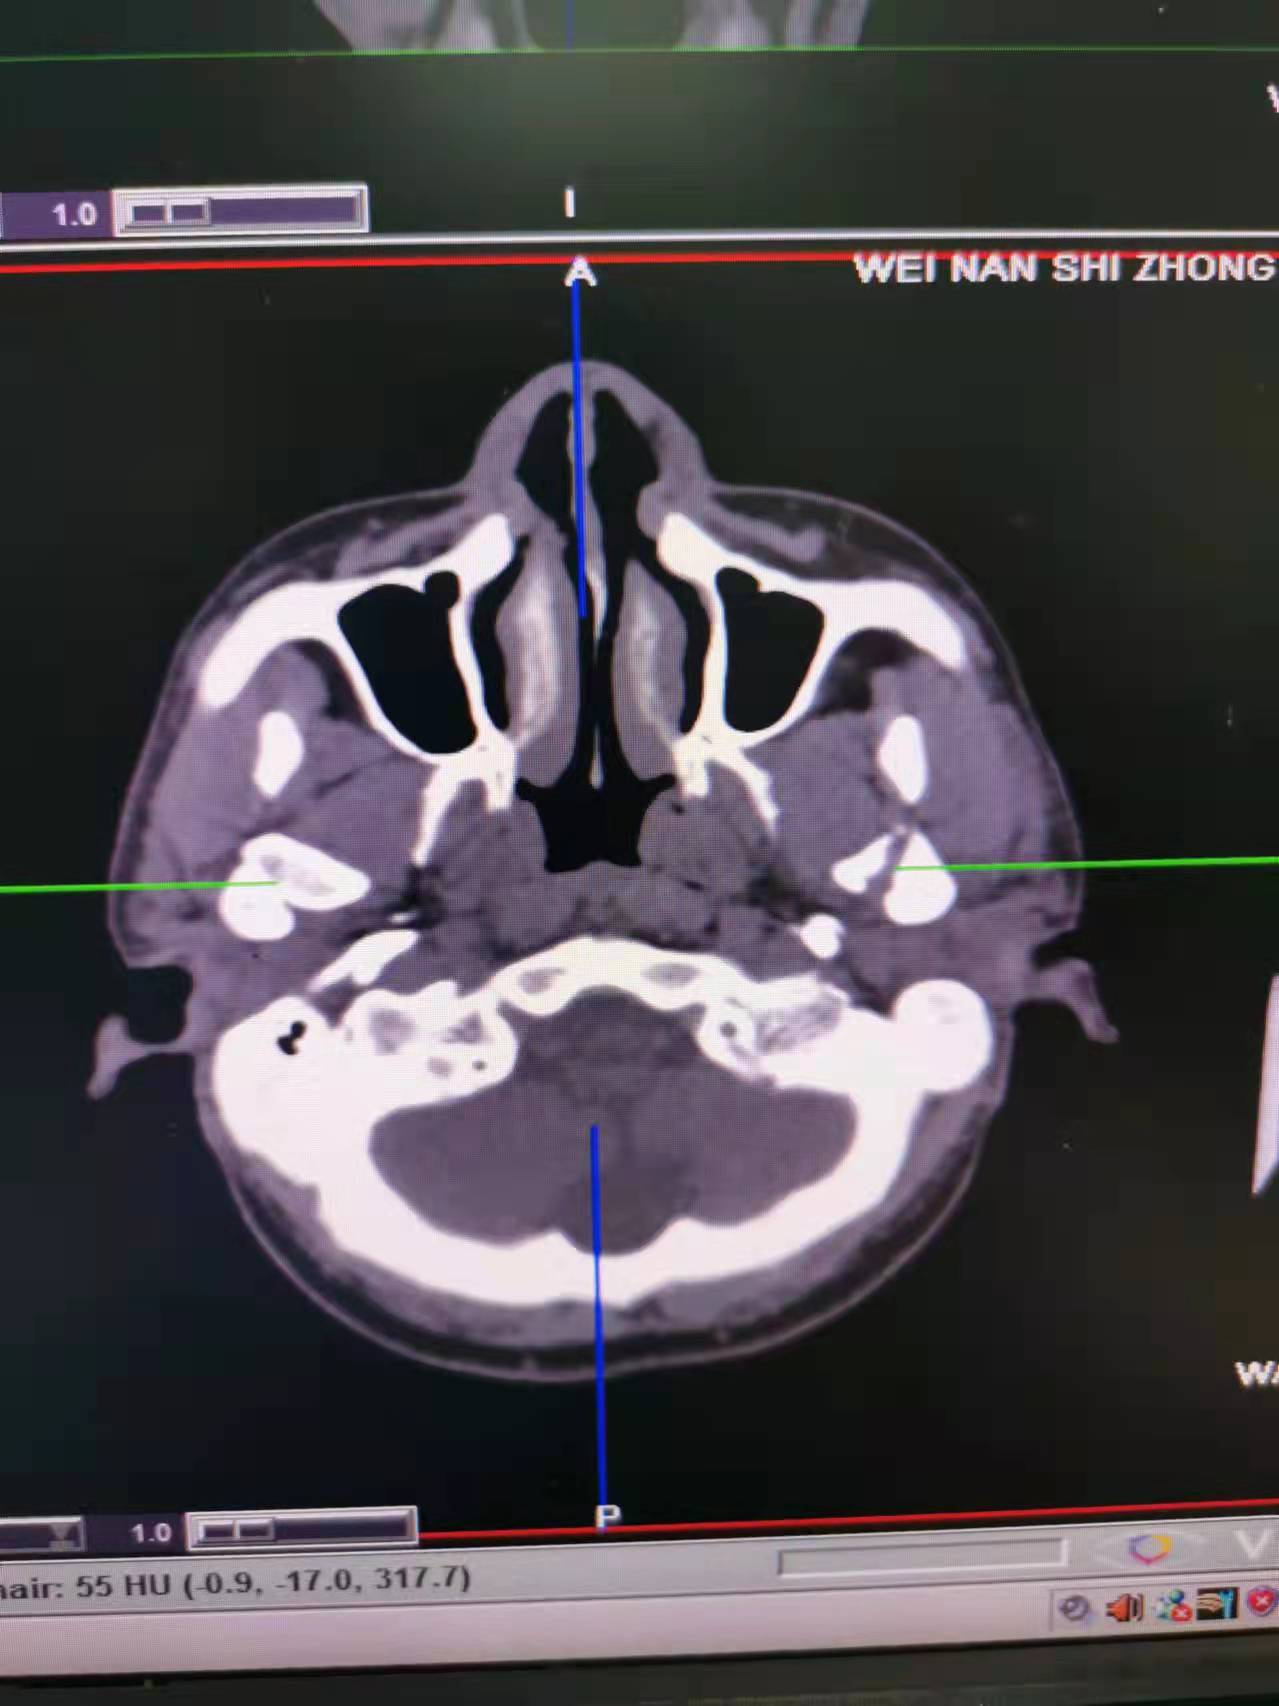

据了解,53岁的患者刘先生在1月25日当天走路不慎摔倒致下颌损伤,造成颏部软组织裂伤和张口困难,前往当地卫生院进行颏部裂伤清创缝合术。术后辗转到乐鱼在线登录入口口腔科门诊就诊,并进行颌面部CT检查提示为下颌颏部正中和双侧髁状突骨折,双侧下颌升支高度不一致,右侧较左侧变短1cm,张口重度困难,咬合关系错乱。刘先生因考虑在春节过后再入院治疗,于2月8日再次前来口腔科以“下颌骨骨折”收治人院。

口腔科主治医师蔺非非为患者入院后进行完善术前常规检查和颌间牵引恢复咬合关系。科主任李瑞春结合患者实际病情和检查结果认为,患者的髁突骨折在下颌骨骨折中所占比例较高,约为17.0%-36.3%。髁突骨折时,耳前区有明显的疼痛,局部肿胀、压痛。通过手指深入外耳道或在髁突部触诊,如张口时髁突运动消失,可能有骨折段移位。双侧低位骨折时,2个髁突均被翼外肌拉向前内方,双侧下颌支被拉向上方,可出现后牙早接触,前牙开秴。髁状突骨折易引起下颌后缩,张口困难,咬合关系错乱,关节强直等并发症。考虑患者系陈旧性骨折应尽早实施手术,避免骨折导致的张口困难、关节强直等并发症。因患者已经错过最佳治疗时期,决定尽快为患者进行手术治疗。

科主任李瑞春和主治医师蔺非非经过缜密的术前讨论和充分评估,手术在全身麻醉下进行,术中克服术野狭小操作不便困难,将下颌骨骨折完好对位,顺利地完成了"双侧髁状突和下颌颏部正中骨折切开复位内固定术"。术后检查患者面部对称,双侧下颌升支高度一致,咬合关系已恢复。